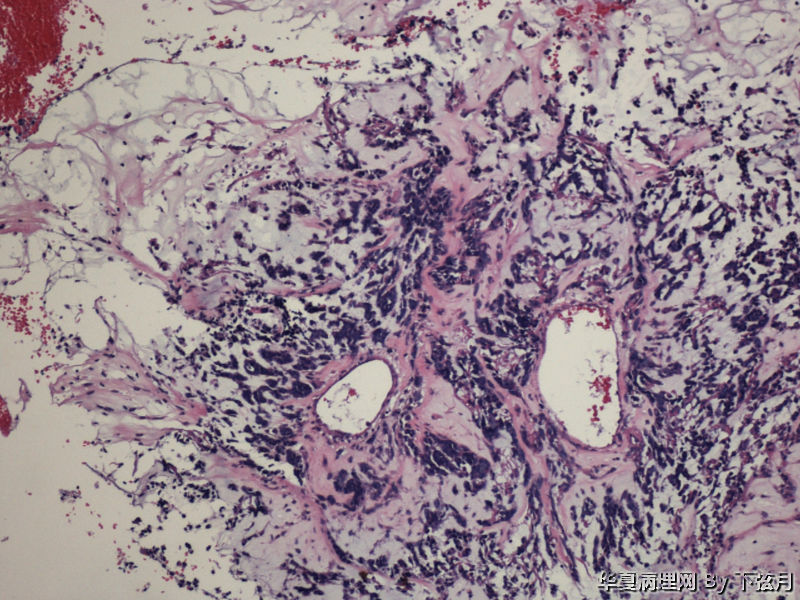

左侧颞叶及胼胝体膝部占位图4

名称:图4

描述:HE 100-3

从图1可见肿瘤似位于脑皮质外围,有粘液背景,部分如脊索瘤样,倾向于脊索瘤样脑膜瘤。

考虑黏液型乳头状室管膜瘤

丰富黏液背景,漂浮乳头状或簇状分布的瘤细胞,免疫组化GFAP,S-100阳性。

有血管轴乳头,粘液样物中漂浮的细胞呈团块状和小乳头状。支持粘液型乳头状室管膜瘤。